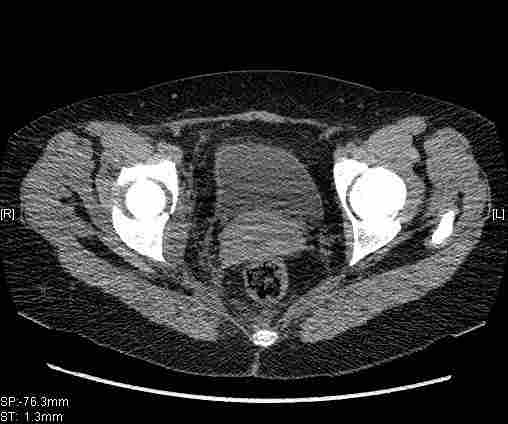

Женщина,58 лет, после ДТП 6 суток. Первично повреждение расценено как переломы ветвей лонной кости. После подтверждения повреждения вертлужной впадины,как чаще всего случается, вопрос встал о тактике. БОльшинство за консерватиное лечение.К сожалению кт у нас "во время" сломался. Прилагаю стандартные снимки вертлужки. У меня следующие вопросы к коллегам:1. Правильно ли рассценивать это повреждение как Т-образный перелом вертлужнй впадины?2. Можно ли добиться анатомической репозиции поверхности вертлужной впадины скелетным вытяжением в данном случае, если нет, что будет этому препятствовать?3. Если смещение останется таким как сейчас, через какое время появится необходимость эндопротезирования (по вашему опыту)?Спасибо.

Удалось сегодня вывести пациентку в соседнюю больницу, где есть кт. Срезы сделаны только горизонтальные.

Следом 3d